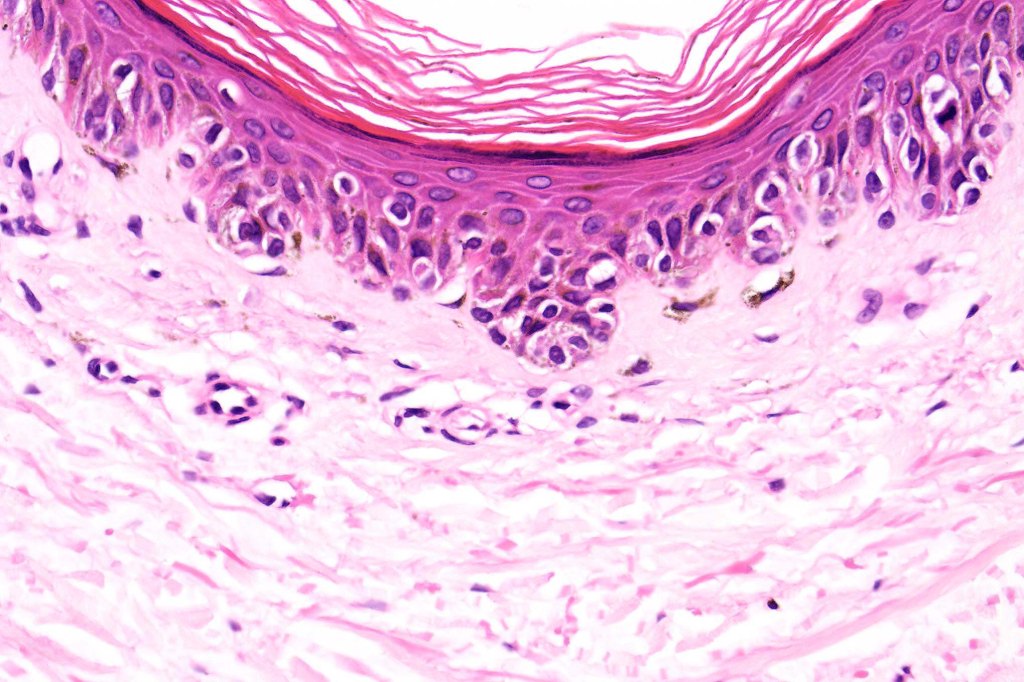

Histological features

- A broad lentiginous proliferation of atypical melanocytes unasscoiated with any loss of the rete ridges

2. Melanocytes generally small, epithelioid (rather than spindled) with either vesicular nuclei and prominent nucleoli or are hyperchromatic.

3. The cells can be present singly, in short pallisades or can extend along a large section of epidermis

7. Fibroplasia not seen and elastosis is either mild or absent